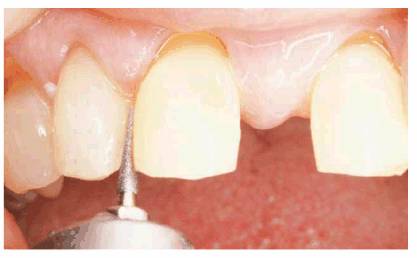

TREATMENT: The teeth were slightly reproportioned by stripping and

disking the distal surfaces of the central and lateral incisors (see Figure 23-10B). The key to successful restorative

diastema closure is creating the illusion of a believable "natural"

tooth width in the central and lateral incisors. Figure 23-10C shows a narrower width of the

central incisors after the distal surfaces have been sufficiently reduced and

ready for full-veneer bonding to close the central incisor diastema and restore

the cervical defects. Final restoration is seen in Figure 23-10D

Figure 23-10B: Stripping and disking of the distal surfaces of the central and lateral incisors were done to slightly reproportion the teeth.

Figure 23-10C: The narrower width of the central incisors readies the diastema for closure.

Figure 23-10D: The final full-veneer bonding closed the diastema and restored the cervical defects.